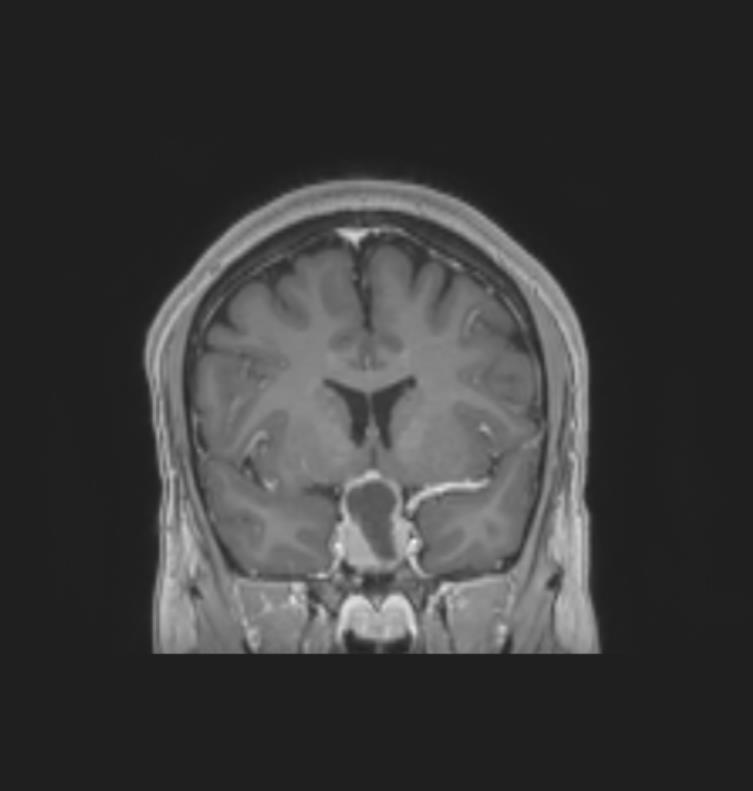

Le patient bénéficie également d’une imagerie par résonance magnétique (IRM) cérébrale devant un doute sur le scanner. Voici deux coupes (figures 2 et 3) :

Figure 3 (source : G. Kielwasser)

Figure 3 bis (source : G. Kielwasser)

Sur cette coupe sagittale en T1 avec injection de gadolinium (figure 3 bis), on observe les mêmes structures que sur la coupe précédente, avec la flèche jaune pointant le macroadénome hypophysaire hémorragique et la ligne rouge représentant la limite virtuelle de la loge pituitaire. La flèche verte pointe le chiasma optique comprimé par la masse.